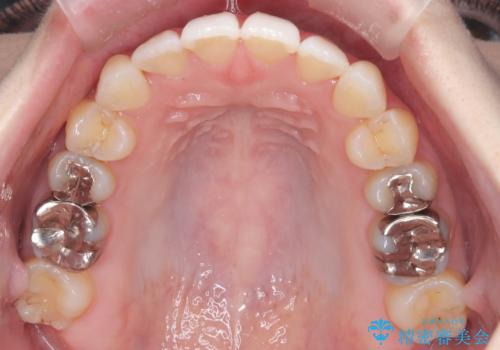

- 前歯のガタガタを主訴に来院された患者様です。

前歯の傾きも少し内側に入るように計画をたて、インビザラインにて治療を行いました。

このぐらいのガタガタであれば、インビザラインで簡単に治すことができます。